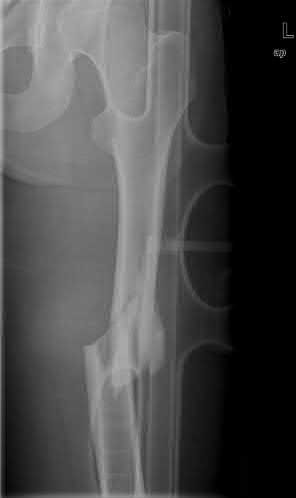

A 25-year-old female is involved in a motor vehicle collision. She presents with the isolated injury seen in Figures A through D. Her leg is swollen but her skin is intact. She has no clinical signs of compartment syndrome. Which of the following treatment options will allow for maintenance of fracture alignment and minimize the risk of soft tissue complications?

The patient presents with a closed distal third metaphyseal-diaphyseal distal tibia fracture with simple intra-articular extension. Immediate intramedullary nailing along with percutaneous fixation of the articular component provides appropriate restoration of length, rotation and alignment and minimizes the risk of wound complication.

Displaced distal third tibia fractures may be associated with simple intraarticular extension. Operative treatment of intra-articular distal tibia fractures has historically been performed with open reduction and internal fixation. Early open reduction and plate fixation of pilon fractures has been associated with high rates of infection and wound complication. In select patterns with simple articular extension, percutaneous screw fixation and medullary nailing may provide appropriate reduction with minimal soft-tissue risk.

Figures A and B demonstrate a distal third tibial shaft fracture with simple intra-articular extension. The axial and coronal CT cuts in Figures C and D further clarify the articular injury. Illustrations A and B demonstrate a comminuted distal third tibial fracture with simple intra-articular extension. Illustrations C and D are fluoroscopic images of the same injury after intramedullary nailing and percutaneous fixation of the articular component.